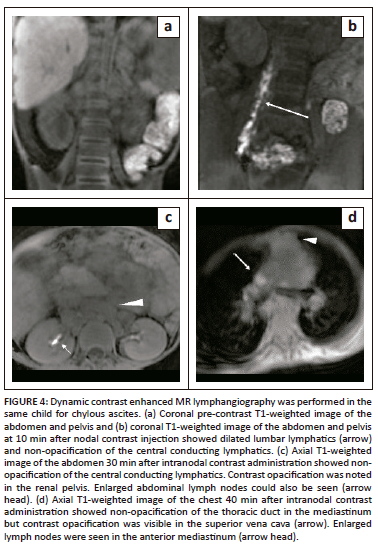

Dynamic contrast enhanced MR lymphangiography was performed after ultrasound guided cannulation of the inguinal lymph nodes. Dilute gadolinium-based contrast was injected on the MRI table. The scan revealed dilated bilateral lumbar lymphatics that were opacified within a few minutes of contrast injection with non-opacification of the cisterna chyli (Figure 4b). Contrast accumulation was seen in the pelvic free fluid on subsequent images (Figure 5). The CLLs remained unopacified on delayed phase imaging due to compression by enlarged retroperitoneal lymph nodes (Figure 4c and d).

In the presented scenarios, the first child presented with milky drain output after resuming feeds post-surgery likely due to intra-operative injury to the lymphatic channels. The second was a case of disseminated tuberculosis with chylous ascites, likely because of obstruction of lymphatic flow secondary to enlarged lymph nodes causing compression and increased back pressure with resultant lymphatic fluid extravasation. It is important to delineate the site of disruption or obstruction and alert the surgeon or radiologist to guide management. It is also imperative to discern whether or not the central conducting lymphatics are involved as they are less likely to respond to conservative management.2,3,4

Variable findings can be seen on MR lymphangiography depending on the aetiology of chylous ascites and the level of occlusion or leak, which may involve the intestinal lymphatics, cisterna chyli or lower thoracic duct. Extravasation of contrast into the peritoneal cavity may also be seen.5 Dynamic contrast-enhanced MR lymphangiography is more sensitive than radiographic lymphangiography in establishing the site of the leak because of the lower viscosity of gadolinium-based contrast agents compared to ethiodised oil. However, in more than half of the cases, the leak site may not be established. This is because the cisterna chyli receives supply from the intestinal, hepatic and bilateral lumbar lymphatics, and it is the lumbar lymphatics that receive direct drainage from the inguinal nodes while the intestinal lymphatics are off track and distant from the site of injection.2,5 However, establishing the integrity of the central conducting lymphatics is crucial for management decisions.

In the first case, there was no evidence of injury to the cisterna chyli or thoracic duct on MR lymphangiography. As a result, surgery was performed and embolising agents were injected into the mesenteric nodes to target the distal intestinal lymphatics. In the second case there was non-opacification of the CCLs cranial to the renal hilum due to compression by enlarged abdominal lymph nodes. The patient was commenced on anti-tuberculous therapy with close monitoring and there was a gradual reduction in chylous output.